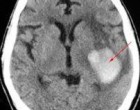

Az orvosi vizsgálatok után Brianna megtudta, hogy férje mit csinált. A vizsgálatok azt mutatták, hogy Austin hosszabb ideig, rendszeresen energiaitalt fogyasztott, hogy jobban bírja a késői munkát. A stimuláló italok rendszeres fogyasztása többek között szívproblémákhoz és magas vérnyomáshoz vezethet, de Austin esetében agyi vérzést okozott.

Egy 5 órás műtét során az orvosoknak sikerült megmenteniük a férfi életét, de ez csak egy nagyon hosszas és kemény munka kezdete volt. Austin számos infarktust szenvedett, és többször újra kellett éleszteni. Koponyájának elülső részét is el kellet távolítani, ami nagyon zavaró látvány. Szinte hihetetlen, hogy egy ember még mindig életképes ebben az állapotban.